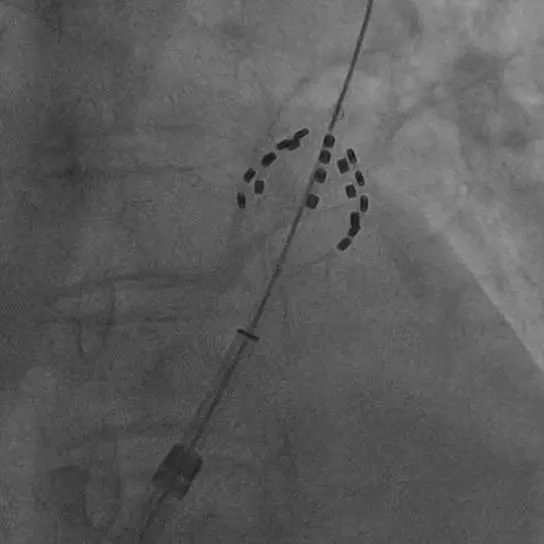

该手术首先通过先进的影像技术进行房间隔穿刺,建立左心房通路将导管送入患者左心房,然后利用三维标测系统对患者的心脏进行详细的三维模型重建,确定左心房的具体位置和范围。接着,运用特殊的脉冲电场消融设备,向心脏特定区域释放短暂而高强度的电场脉冲。脉冲精准地破坏房颤病灶,同时最大程度地减少对周围正常组织的损伤。

与传统的射频消融相比,脉冲消融不需要持续加热心肌组织,从而降低了手术过程中对心脏组织的热损伤风险,极大提高了手术的安全性。将消融导管分别送入四个肺静脉开口实施脉冲电场消融,前后不到20分钟,4个肺静脉的电传导即被彻底阻断,肺静脉电位完全消失。